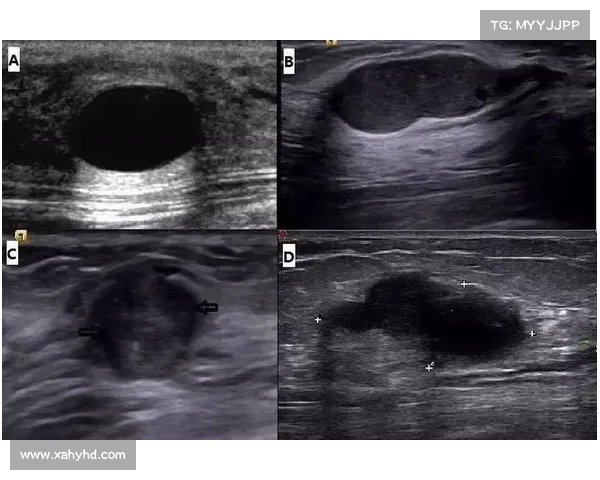

结节是指体内某个器官或组织局部的体积增大,形态呈肿块状。结节的大小、位置、形态、密度等特征各异,因此它们可以出现在多种不同的器官中,如甲状腺、肺部、乳腺、肝脏等。

- 良性结节:良性结节的特点通常是边界清晰、形态规则,且生长缓慢,通常不会引发严重的健康问题。常见的良性结节如甲状腺结节、乳腺良性肿块等。

- 恶性结节:恶性结节则通常形态不规则、边界模糊,生长迅速,可能会侵犯周围组织或转移到其他部位。恶性结节如肺癌、乳腺癌等。

- 甲状腺结节:甲状腺结节是一种常见的体检发现,尤其是在超声检查中。大多数甲状腺结节为良性,如腺瘤或囊肿。甲状腺结节的恶性几率相对较低,但需要通过甲状腺功能测试、细针穿刺活检等进一步诊断。

- 乳腺结节:乳腺结节也很常见,尤其是女性。乳腺结节大部分为良性,如纤维腺瘤或囊肿。只有少数结节可能是乳腺癌的早期表现,尤其是结节的形状不规则、边界模糊时,可能需要进一步的影像学检查或穿刺活检。

囊肿是指体内某些部位形成的充满液体的囊状结构。它们常见于乳腺、卵巢、肾脏、肝脏等部位。囊肿在体检中也经常被发现,许多人担心囊肿会发展为癌症,但大多数囊肿都是良性的。

- 乳腺囊肿:乳腺囊肿是最常见的乳腺良性病变,通常与激素水平波动有关。乳腺囊肿一般是无症状的,除非囊肿较大或发生感染。大多数乳腺囊肿无需治疗,但需要定期随访。

- 卵巢囊肿:卵巢囊肿在女性中非常普遍,尤其是在育龄期。大多数卵巢囊肿是良性的,如功能性囊肿,但也有少数囊肿可能与卵巢癌有关。因此,定期检查和随访非常重要。